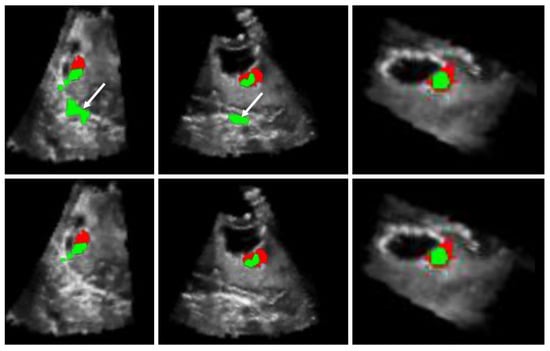

Figure 10 depicts an example where extra regions, here the falx, are identified by the fusion method. These structures are obviously not tumorous tissue because they are located far from the resection cavity. Moreover, the elongated and indented shape of the extracted region is not characteristic of tumor residuals whose shape is rather compact. However, this area was enhanced in the 3D iB-mode and iCEUS image data and therefore extracted by the algorithm. A semi-automatic approach could be suggested by interactively defining a region of interest enclosing the surrounding of the resection cavity in order to limit the search volume of tumor residuals. Furthermore, Figure 10 gives an illustration of the results reached with the automatic and semi-automatic methods for a specific case. The first and second rows show the results obtained by using the automatic and semi-automatic methods, respectively. The automatic method result is sufficient for the neurosurgeon, because he/she refers to his knowledge to extract the correct information among the set that the algorithm suggests. Moreover, the semi-automatic process could be automated by extracting the hole of the cavity.

Figure 10.

Results of residual tumor identification from Patient 4: automatic versus semi-automatic approaches. The automatic proposed method where the white arrows show extra regions detected by the algorithm (Row 1). Correction of over residual tumor identification by using a semi-automatic method based on an ROI (Row 2). The algorithm outcomes (in green) are superimposed with the expert manual segmentation (in red).